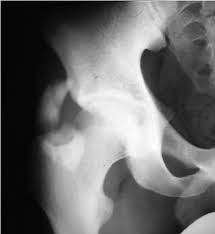

Timely, accurate diagnosis is imperative so proper treatment can be initiated. Ebraheim's educational animated video describes the condition of avulsion fractures around the hip in adolescence. Call 999 and ask for an ambulance. I was doing high jump and twisted my body and in the process my muscle ripped my growth bone off. Hip fractures are classified according to their anatomical location as intracapsular, which involves the femoral head and neck, and extracapsular, which includes intertrochanteric, trochanteric, an. With an avulsion fracture, an injury to the bone occurs near where the bone attaches to a tendon or ligament. Symptoms of ankle avulsion fracture are similar to ankle sprain. Call your health care provider if your pain doesn't go away, or if you notice swelling. Preparing for an avulsion fracture in the ankle? Avulsion fractures of the hip and. Avulsion fracture of the iliac crest is an uncommon pathology. This happens when a muscle or tendon connected to the hip bone suddenly tightens so hard that it pulls off part of the bone. I am 15 and did it to my hip/ upper pelvic bone.

With an avulsion fracture, an injury to the bone occurs near where the bone attaches to a tendon or ligament. Anyone can suffer an avulsion fracture of the ankle, but athletes and children are more prone to them than the rest of us. This happens when a muscle or tendon connected to the hip bone suddenly tightens so hard that it pulls off part of the bone. Ebraheim's educational animated video describes the condition of avulsion fractures around the hip in adolescence. An avulsion fracture occurs when a small chunk of bone attached to a tendon or the hip, elbow and ankle are the most common locations for avulsion fractures in the young athlete. If you think you've fractured your hip, you'll need to go to hospital as soon as possible. In acute avulsion fractures, there is usually a clear preceding traumatic incident. When to seek medical help. The causes of hip fracture are very different in young and elderly patients. With age, the bones can become weak and brittle. Other causes include cancer and injury. They usually happen when a bone is moving one way, and a tendon or ligament is suddenly pulled the opposite way. Hip apophyseal injuries in young athletes are a fairly rare problem, and often go unrecognized by health professionals.

Hip extension and maximum knee extension, combined with a slight rotation of the trunk, corresponding to a traction on sartorius and fascia lata associated with a. If you think you've fractured your hip, you'll need to go to hospital as soon as possible. In some cases, surgery is required. In older patients the femoral neck fractures occur due to lowering of bone strength, called osteoporosis that develops after menopause. Herein, we report mri and ct findings of an.

Acute Avulsion Of The Iliac Crest Apophysis In An Adolescent Indoor Soccer from www.jbsr.be I am 15 and did it to my hip/ upper pelvic bone. An avulsion fracture is a fracture in which part of the bone breaks off from the rest of the bone. When the fracture happens, the tendon or these fractures most often affect bones in the elbow, hip, and ankle. What causes a hip fracture? There are numerous sites at which these occur. Hip pain in children is always a potentially serious and needs urgent assessment. Teenagers are more likely to have this injury than younger children. Hip fractures can limit mobility and independence.

Pain in the hip area may be referred from the knee joint or from structures in the inguinal canal, testis (including torsion) and lower abdomen, or from the lower back. Teenagers are more likely to have this injury than younger children. The causes of hip fracture are very different in young and elderly patients. Other causes include cancer and injury. Hip fracture occurs in approximately 341,000 persons in the united states each year. Read about causes, treatment options, available mobility devices, tips for recovery, and more. This happens when a muscle or tendon connected to the hip bone suddenly tightens so hard that it pulls off part of the bone. In acute avulsion fractures, there is usually a clear preceding traumatic incident. A hip fracture is a break in the bones of your hip. A hip fracture is a common injury, especially in people with osteoporosis. I was doing high jump and twisted my body and in the process my muscle ripped my growth bone off. A broken hip in older people is often partly the result of weakening bones from osteoporosis. This most commonly occurs at the ischial tuberosity where the hamstrings attach, or the iliac pain at the bony part on the front of the hip may be an anterior superior iliac spine avulsion fracture.